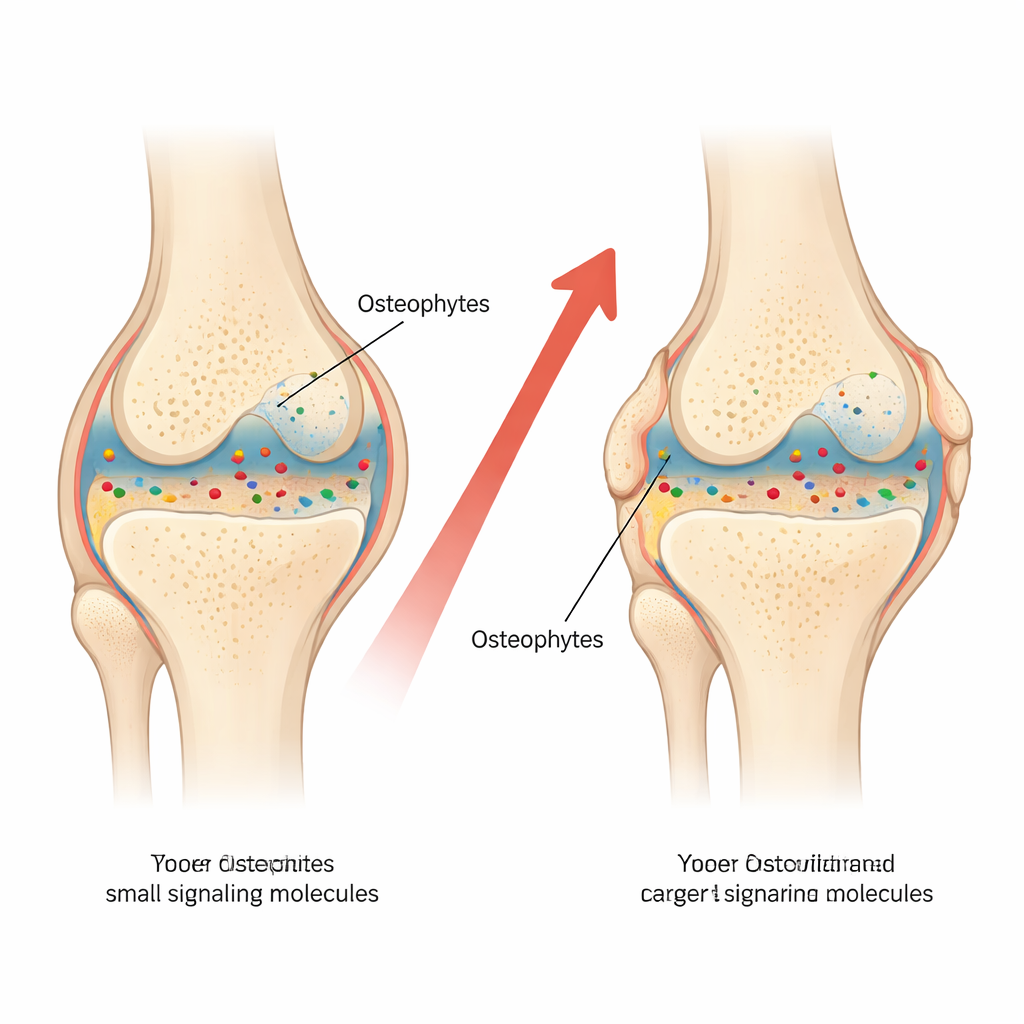

Molte persone con artrite del ginocchio di lunga durata sviluppano noduli duri e ossei attorno all’articolazione, spesso chiamati osteofiti o speroni ossei. Queste escrescenze possono limitare il movimento e aumentare il dolore, eppure i medici discutono ancora sul perché si formino e su come si colleghino alla malattia di base. Questo studio ha esaminato l’interno di ginocchia gravemente danneggiate per verificare se i segnali chimici dell’infiammazione nel liquido articolare siano correlati alle dimensioni di queste escrescenze ossee, offrendo indizi sia sui meccanismi della malattia sia su possibili trattamenti futuri.

Sono emersi diversi schemi chiari. Primo, i livelli di IL‑18 nel sangue erano fortemente correlati a quelli di IL‑18 nel liquido articolare, suggerendo che l’infiammazione all’interno dell’articolazione può riversarsi nella circolazione. Nel liquido articolare stesso, livelli più elevati di IL‑18 tendevano a associarsi a osteofiti più grandi sia sul femore sia sulla tibia. Questa relazione è rimasta anche dopo aver tenuto conto dell’età e del peso dei pazienti, soprattutto per gli speroni sul femore. Al contrario, le altre due molecole—MMP‑1 e IL‑8—non hanno mostrato una connessione significativa con la dimensione degli osteofiti in questo gruppo di pazienti gravemente colpiti. L’età risultava correlata a osteofiti più ampi, mentre l’indice di massa corporea e l’allineamento della gamba non lo erano, forse perché tutti i partecipanti avevano già una malattia in fase avanzata.

Infiammazione, chimica locale e crescita ossea

Il fatto che solo IL‑18 nel liquido articolare—e non nel sangue—si sia correlato con la dimensione degli osteofiti indica l’importanza dell’ambiente chimico locale all’interno del ginocchio. Si pensa che gli osteofiti sorgano quando i tessuti articolari sotto stress inviano segnali che innescano un processo simile all’attività della piastra di crescita nelle ossa dei bambini. Dalla ricerca precedente si sa che IL‑18 influenza le cellule che formano l’osso e quelle che costituiscono la cartilagine. Gli autori suggeriscono che livelli più alti di IL‑18 nel liquido articolare non siano necessariamente la causa unica degli speroni ossei, ma rappresentino un contesto attivo e ricco di infiammazione che favorisce una crescita ossea anomala ai margini articolari.